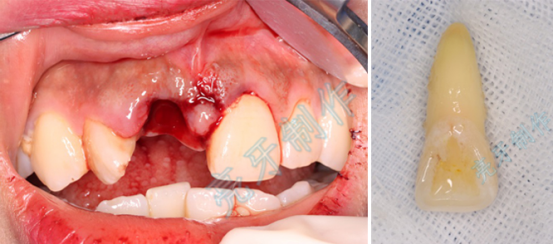

病例三:牙齿嵌入牙槽骨,松动明显,经过治疗,稳定了,也恢复了外形。